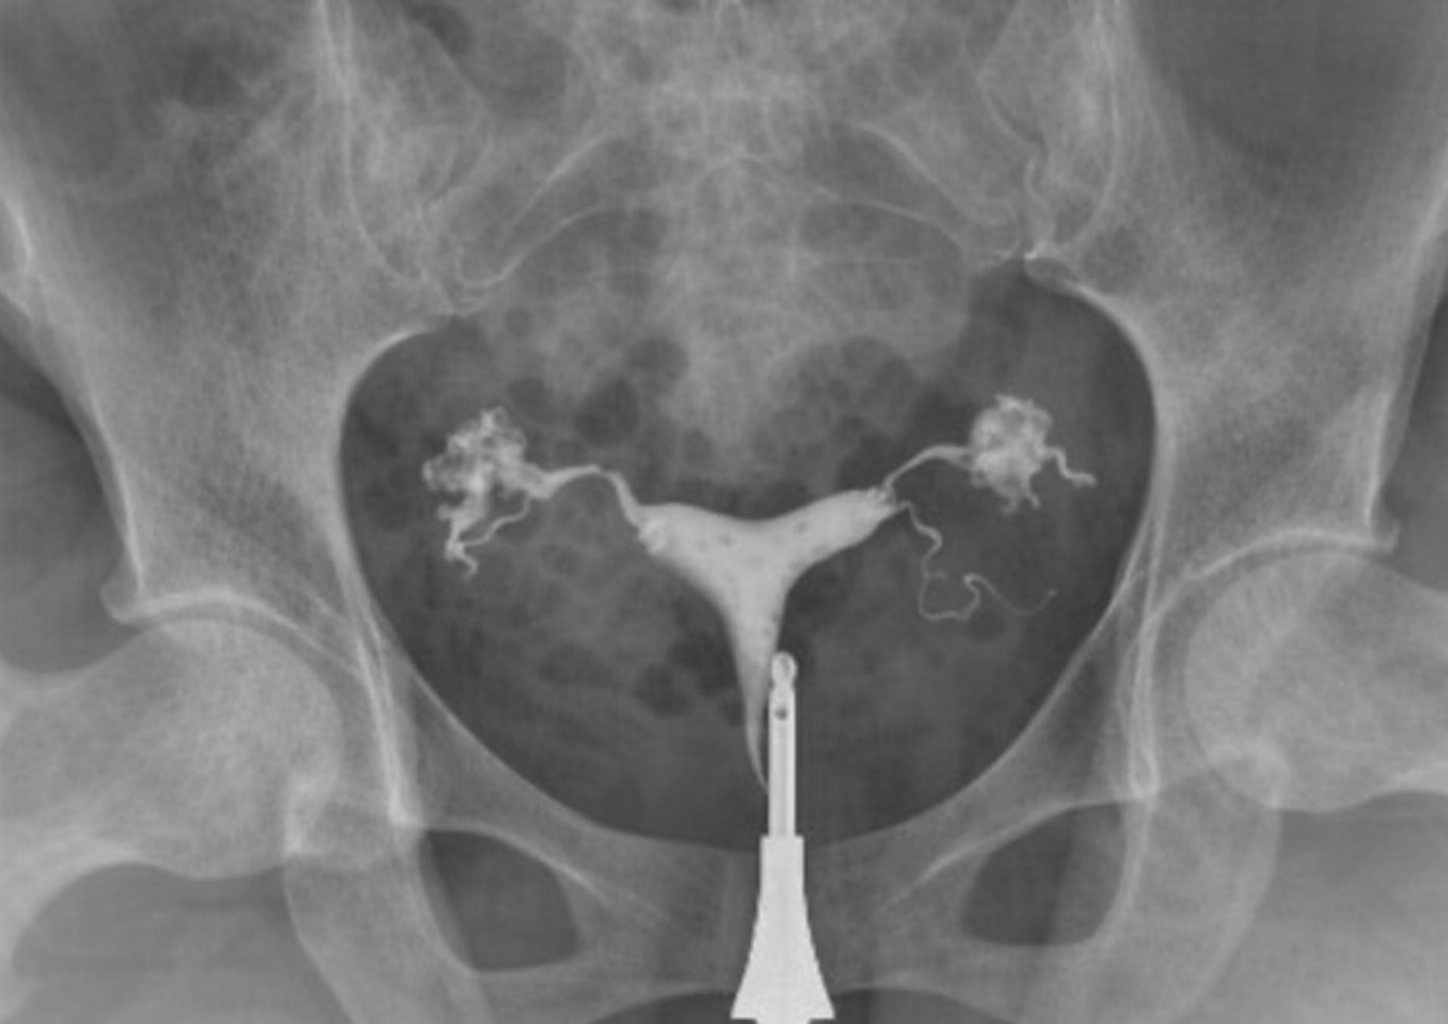

Hidrosalpenks, fallop tüplerinin içinin sıvı ile dolması sonucu oluşan bir durumdur. Genellikle geçirilmiş enfeksiyonlar, pelvik inflamatuar hastalıklar veya tüplerin hasar görmesi sonucunda ortaya çıkar. Bu durum tüplerin normal fonksiyonunu bozarak gebelik oluşumunu zorlaştırabilir.

Hidrosalpenks varlığında tüp içerisinde biriken sıvı zaman zaman rahim içine geri akabilir. Bu sıvı embriyonun rahim duvarına tutunmasını engelleyebilir ve özellikle tüp bebek tedavilerinde başarı oranını ciddi şekilde düşürebilir. Bu nedenle hidrosalpenks tespit edilen hastalarda tedavi planlaması büyük önem taşır.

Tedavi genellikle laparoskopik cerrahi ile gerçekleştirilir. Bu işlem sırasında hasarlı tüp tamamen çıkarılabilir (salpenjektomi) ya da tüpün rahim ile bağlantısı kesilerek sıvının rahim içine ulaşması engellenir. Hangi yöntemin uygulanacağı hastanın durumuna göre belirlenir.